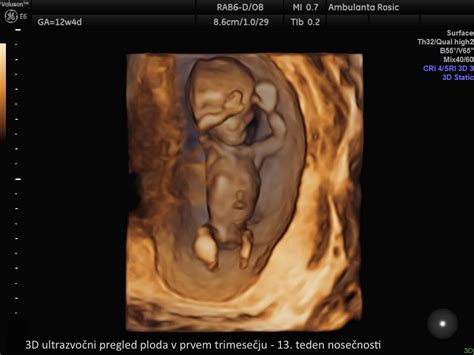

- Prvo trimesesečje (teden 1-13): V tem obdobju se oplojeno jajčece ugnezdi v maternično steno, začne se razvoj vitalnih organov, telo nosečnice pa se prične prilagajati na novo stanje. Pogosti so simptomi, kot so utrujenost, slabost in občutljive dojke. V tem času se opravijo tudi prvi ključni pregledi, vključno z določitvijo krvne skupine in Rh faktorja, ter ultrazvočna potrditev nosečnosti.